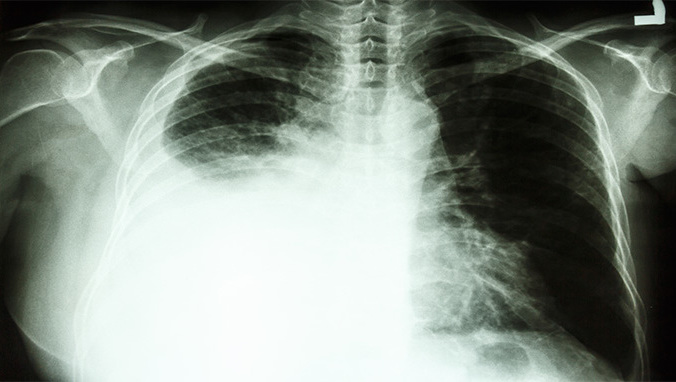

纵隔肿瘤是临床胸部常见疾病,包括原发性肿瘤和转移性肿瘤。原发性纵隔肿瘤包括位于纵隔内各种组织结构所产生的肿瘤和囊肿,但不包括从食管、气管、支气管和心脏所产生的良、恶性肿瘤。转移性肿瘤较常见,多数为淋巴结的转移,纵隔淋巴结转移病变多见于原发性肺部恶性肿瘤,如支气管癌。肺部以外者则原发于食管、乳房和腹部的恶性肿瘤最为常见。

这种疾病的部分病例可无明显临床症状,体积较大的肿瘤因其压迫或侵犯纵隔内的重要脏器而产生相应的临床症状:如压迫气管则有气促、干咳;压迫食管可引起吞咽困难;压迫上腔静脉导致面部、颈部和上胸部水肿及静脉怒张;压迫神经可有膈肌麻痹、声音嘶哑、肋间神经痛及交感神经受压征象。

良性纵膈肿瘤不会很严重的,多数良性纵膈肿瘤临床上常无症状,多于体检时发现。恶性纵膈肿瘤常见的症状有胸闷胸痛是各种纵膈肿瘤最常见的症状,如果疼痛剧烈,病人难以忍受者多为恶性肿瘤,严重时发生呼吸困难。

即使良性纵膈肿瘤无症状,由于会逐渐长大,压迫毗邻器官,甚至出现恶变或继发感染.因而均以采取手术为宜。恶性纵隔肿瘤若已侵入邻近器官无法切除或已有远处转移,则禁忌手术而可根据病理性质给予放射或化学药物治疗。